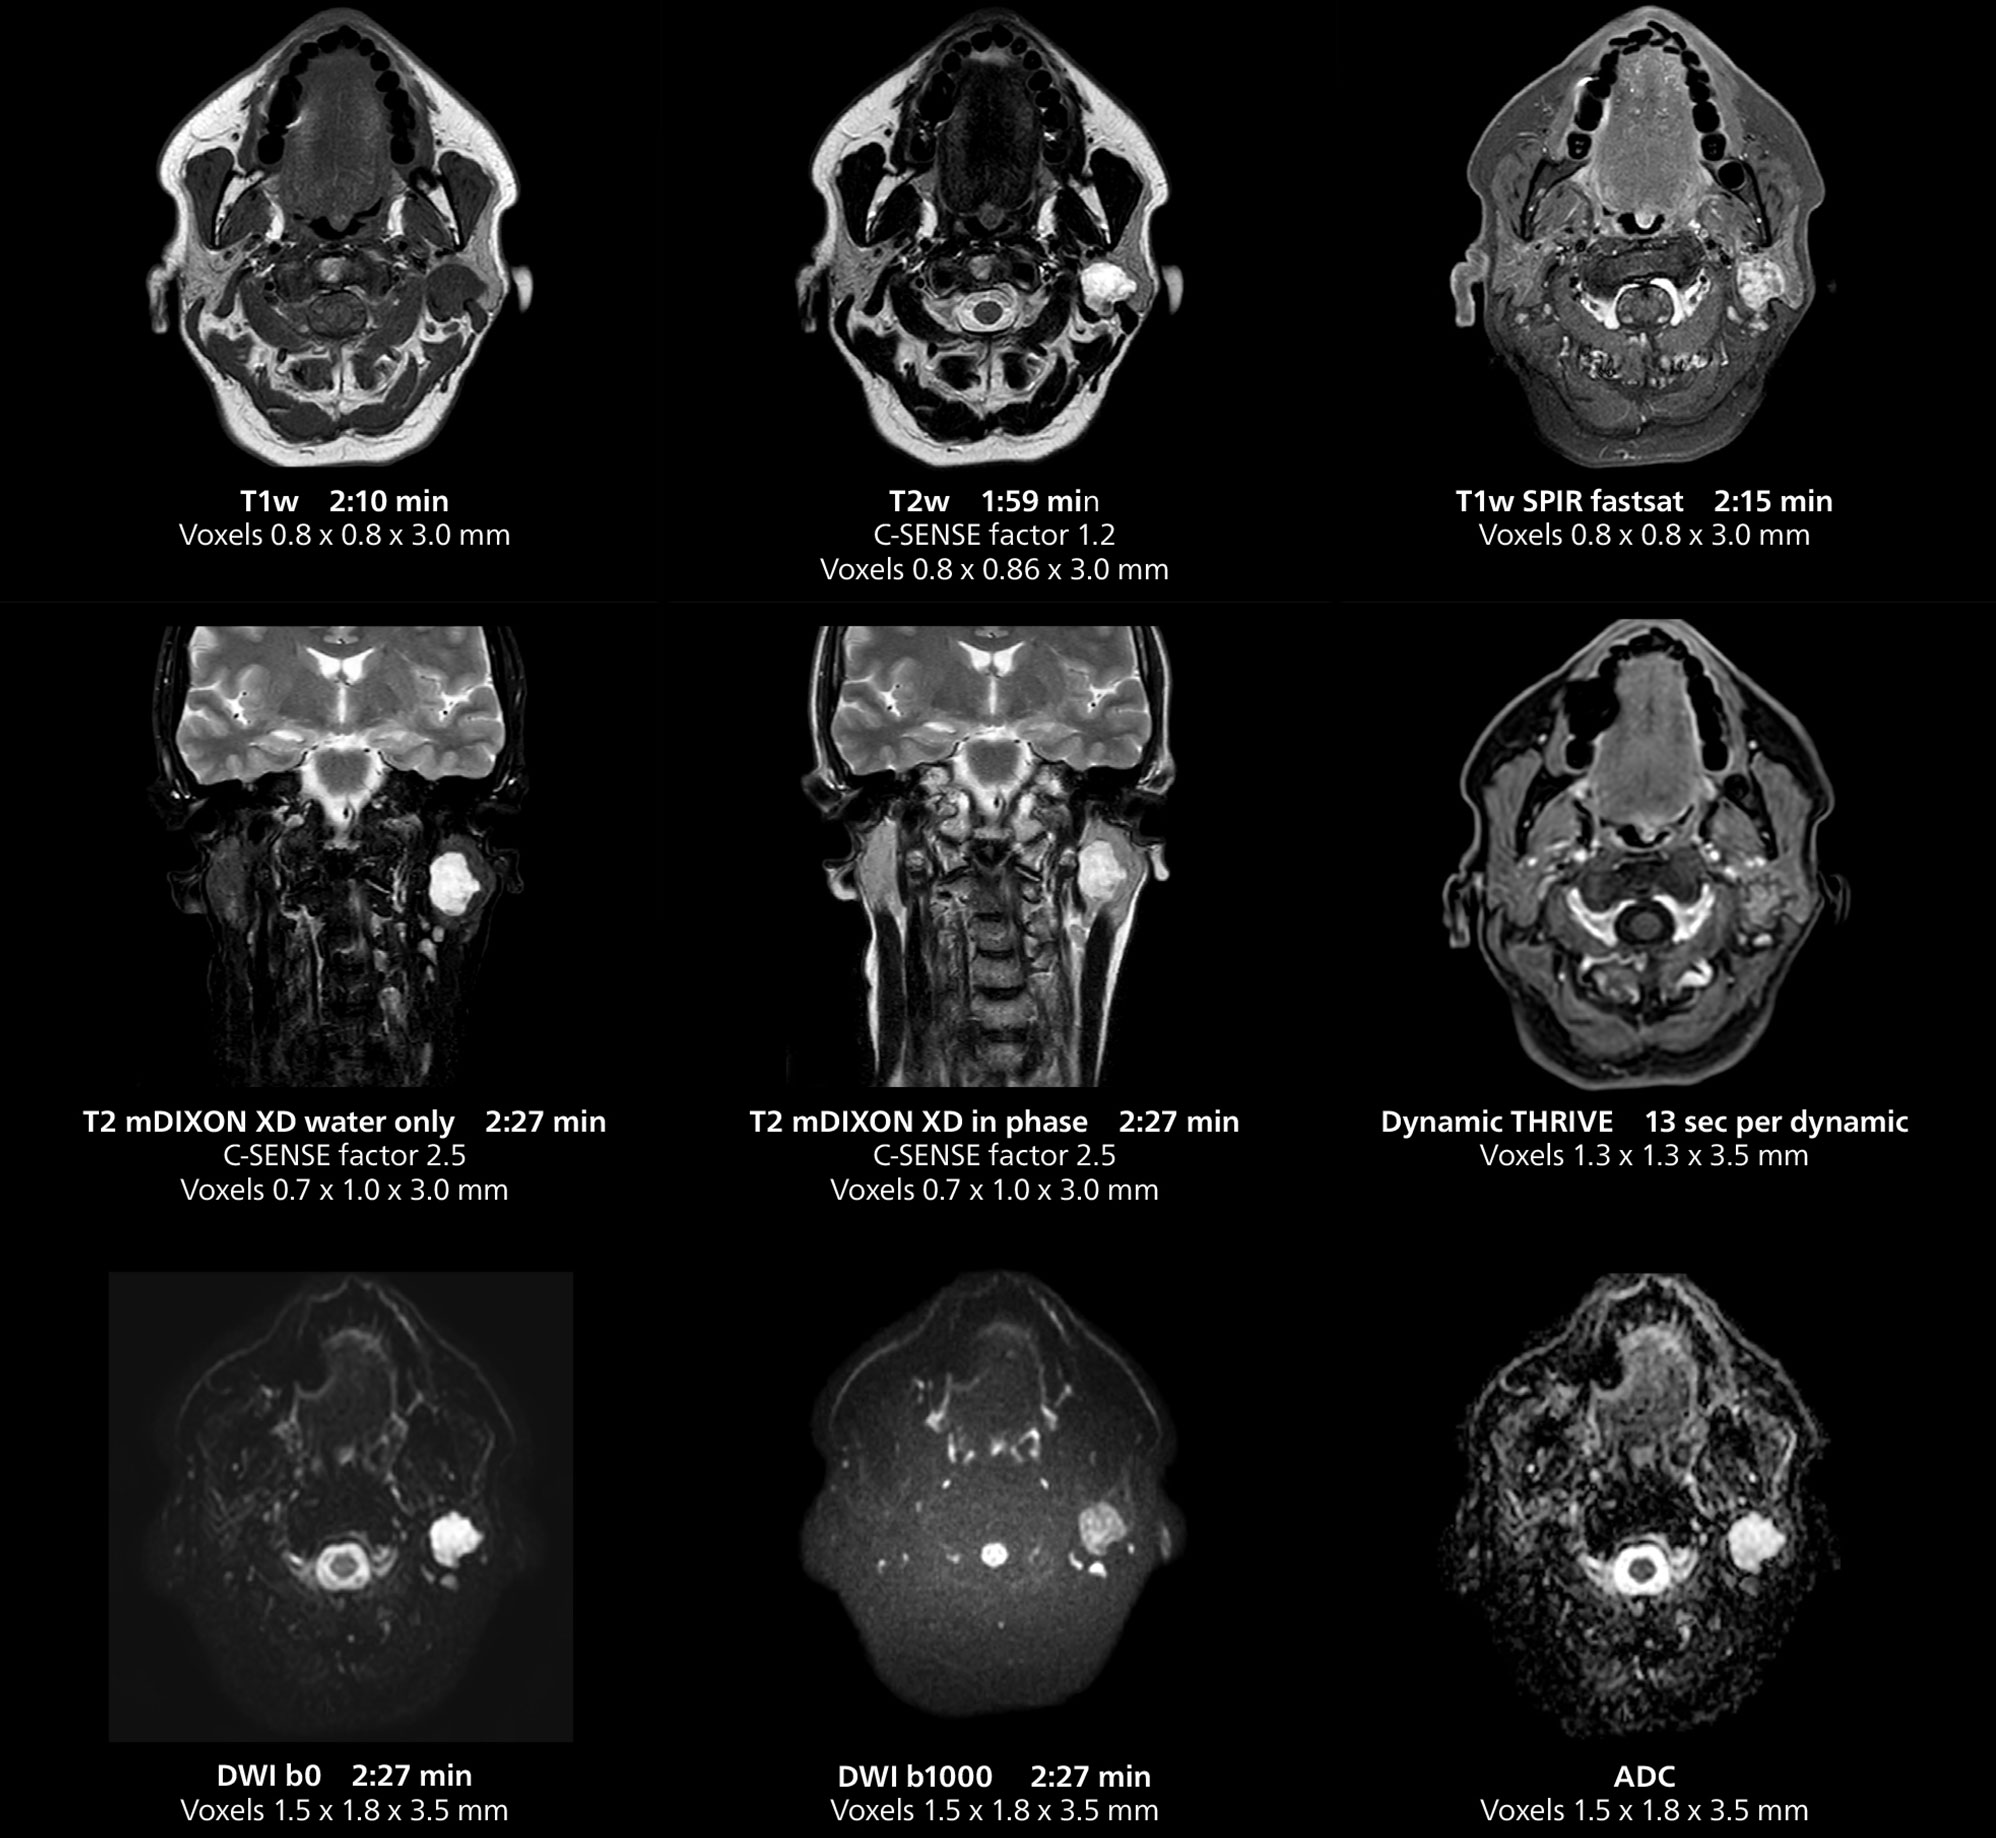

This MRI case illustrates imaging of salivary gland abnormalities with different sequences. Compressed SENSE allows to accelerate scanning while maintaining high quality. With mDIXON XD, different contrast types can be obtained from scanning one sequence.

The MR 5300 with Compressed SENSE is up to 50%** faster for many exams. It can provide routine exams in less than 5 minutes and whole-body exams in less than 20 minutes. Saint-Augustin has taken advantage of that speed to create highly efficient protocols. The hospital’s standard stroke protocol is just about 8 minutes, and standard ENT, prostate PIRADS staging, and endometriosis studies all clock in at just about 10 minutes.***

“We have more speed in 3D sequences,” Dr. Gellée states. “With Compressed SENSE, we can replace two or three 2D scans withone high-quality 3D scan. High quality additional orientations are then obtained by post-processing of the 3D data set, thus saving scanning time.”

Dr. Gellée often takes advantage of the system’s speed to add more sequences to an exam. “When Compressed SENSE reduces typical exam duration, I can add sequences to increase my confidence in diagnosing. For example, post-gadolinium liver scans used to be axial, but now we can use a faster coronal scan. And because I know that the quality will be good the first time, I know I won’t have to repeat the sequence. That frees up time to comfortably add one more sequence,” she says.